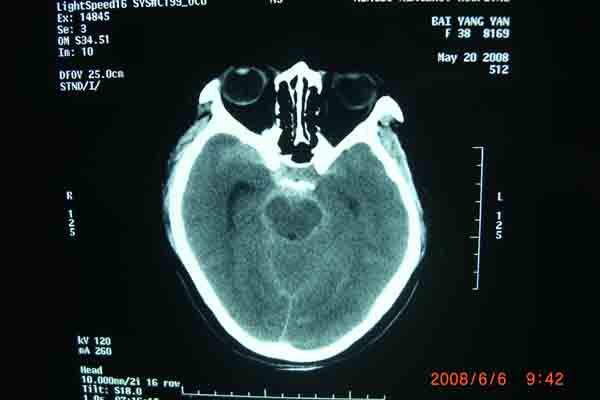

6月6日上午,在明州医院放射科的DSA检查室内。上海的神经外科专家及麻醉科在为一位38岁的云南来宁波打工中年女病人做颅内动脉瘤(眼颈交界处7*3.5cm)血管内栓塞手术。无影灯下,准备工作在有条不紊地进行着。全身麻醉后。介入手术开始了,手术医生以非常娴熟的手法,在右侧股动脉内置入导管,在显像下,随着导丝进入,顺利到达动脉瘤瘤腔内。随着弹簧圈进入,瘤腔内被充填。造影后,显示位置良好。所有的神经外科医生知道,在手术过程中,如果发生动脉瘤破裂,那后果不堪设想。手术成功了,大家悬着的心放下了。整个手术时间仅仅用了1个半小时。手术后,病人即清醒,送回病房。

回想这个病人是5月 20 日,因为在早晨起床后,突然昏迷不醒,跌到在地,被家人送往明州医院急症室,经过医生检查,这个病人已经瞳孔放大,呼吸停止。紧急地插入气管导管后,给予呼吸机使用。经过医院上海神经外科专家检查病人后,指出这是动脉瘤破裂出血导致的呼吸压制。需要头颅CT检查,在捏着皮球保持呼吸道通畅,即刻行头颅CT检查,确认为动脉瘤破裂出血,前交通动脉瘤破裂为主。专家看了片子后,认为如果行双侧脑室外引流,将血液引出,可能会使呼吸恢复。马上送手术室做急症手术,引流出血性脑脊液后,病人呼吸慢慢恢复了。经过3个星期的正规治疗(高血压,高颅压,高体温)(抗血管痉挛,抗感染)(外引流)病人终于度过了危险期。在6月6日上午成功进行了颅内动脉瘤血管内栓塞手术。